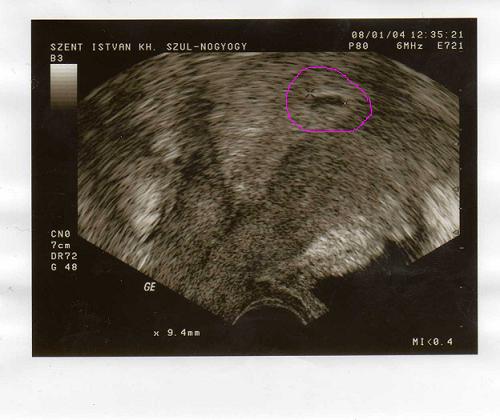

Itt a babóm. 9mn-se petezsák. a rossz hír az hogy nem látni benne még semmit és kicsit szabálytalan szélű amiért ráírta a papírra hogy missed ab gyanúja. Így pénteken megint mehetek de nem fogok addig várni hanem kedden elmegyek az sztkba és ott megnézetem hogy nőtt e

Vera! Visszakerestem, nekem 5 hetesen ennél százszor szabálytalanabb volt mint a te képeden. :D :D Sőt ilyenkor nem is mindig szokott látszani benne a törpike, neked meg teljesen látszik. :D Mi a francot kell már megint kelteni ezeknek a köcsög dokiknak a feszültséget??????? Ezek ezt élvezik????? Mondja azt, hogy még nem látható szívműködés (ennyi idősen nem is) és gyere vissza 1 hét múlva! Addig az ég adta világon semmi se lenne másképp, csak te egy babával a pocidban nem görcsölnél x napig rajta, halál feleslegesen.

Ja még annyit, Vera, hogy szerintem az sztk-snak ne mondd el az előzményt, hogy enélkül ő mit mond!!! És ne vedd készpénznek, hogy mekkorát mér, mert egyrészt másik uh géppel dolgozik, másrészt ekkora manótartó zsáknál csak egy miliméterrel máshova teszi az x-et és máris tök más jön ki, mint amekkora valójában.

Vera! Látom, de az uh fénykép mindig csalóka. Ha ott álltam volna melletted, könnyebben tudnám. De szerintem van benne baba. Én a kép alapján biztos vagyok benne :wink: